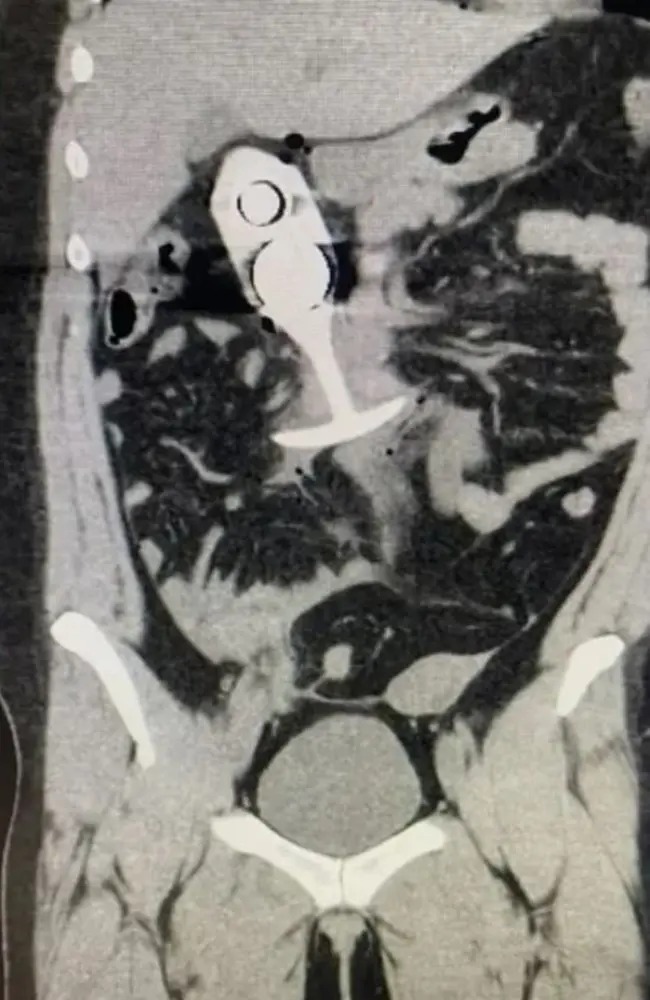

虽然这宗事件发生在2023年4月,但据称显示患者事发后扫描的图像,最近开始在网上流传,提示人们不要在扫描期间佩戴任何金属物品。

▲肛塞穿过女子身体,致她身受重伤。 路透社